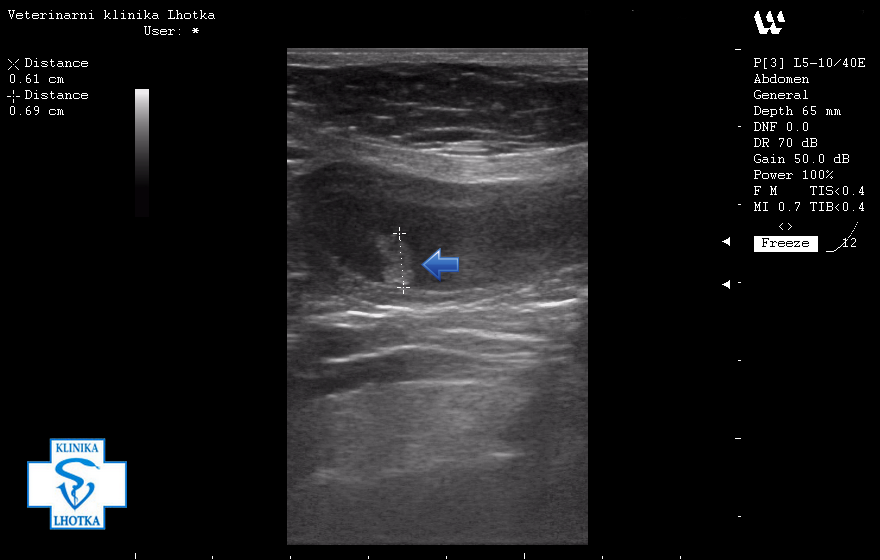

Šipkami je označena zvětšená mízní uzlina v břiše pod bederní páteří.

SONO - zvětšená sublumbární MU